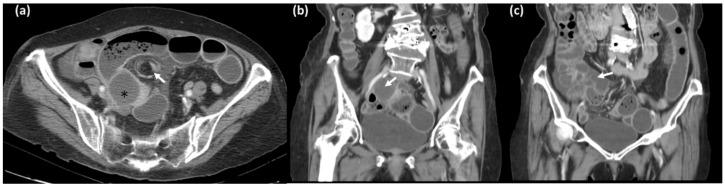

Appendiceal mucinous tumors are rare, with variable malignant potential, and they are usually found incidentally. Clinical symptoms are nonspecific. Rarely, appendiceal mucinous neoplasm causes bowel obstruction and makes diagnosis more difficult. We present a case of an 84-year-old female who came to our emergency department having had abdominal fullness and constipation for 5 days. Ileus, due to an affected adhesion band, was diagnosed initially, and symptoms improved gradually under conservative treatment. However, 3 months later she presented to the emergency department again with abdominal pain and distension; small bowel obstruction due to adhesion was again diagnosed. Recurrent bowel obstruction prompted emergent surgery. Operative findings showed a whitish appendiceal tumor adhering to and directly invading the adjacent ileum, with a segment of herniated small bowel wedged in between, causing the obstruction. Upon reviewing the initial computed tomography scan, the dilated tubular structure of appendiceal tumor was misrecognized as small bowel loop; there was no surrounding inflammatory sign, leading to diagnosis difficulty. Instead of a common cause of bowel obstruction, such as adhesion band, this case revealed bowel obstruction can be caused by the direct invasion of an appendiceal tumor. Awareness of this condition with careful image evaluation of small bowel obstruction is essential for diagnosis.

阑尾黏液性肿瘤较为罕见,恶性潜能各异,通常为偶然发现。临床症状不具特异性。阑尾黏液性肿瘤极少导致肠梗阻,使诊断更加困难。我们报告一例84岁女性患者,因腹部胀满和便秘5天前来我院急诊科就诊。最初诊断为因粘连带导致的肠梗阻,经保守治疗症状逐渐改善。然而,3个月后她再次因腹痛和腹胀到急诊科就诊;再次诊断为粘连性小肠梗阻。反复的肠梗阻促使进行急诊手术。手术所见显示一个白色的阑尾肿瘤附着并直接侵犯相邻的回肠,一段疝出的小肠夹在中间,导致梗阻。回顾最初的计算机断层扫描,阑尾肿瘤扩张的管状结构被误认作小肠袢;周围没有炎症迹象,导致诊断困难。该病例显示肠梗阻并非由粘连带等常见原因引起,而是由阑尾肿瘤的直接侵犯所致。认识到这种情况并对小肠梗阻进行仔细的影像评估对诊断至关重要。